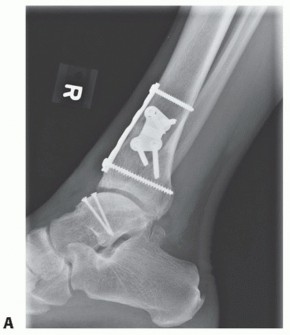

We routinely obtain simulated weight-bearing radiographs at 6 and 10 weeks and again at 14 to 16 weeks, depending on the progression of healing. If there was a concern about fixation of the graft or osteotomy, then radiographs are also obtained at the first postoperative visit (FIGS 1 , 2 and 3).

FIG 1 • Two-and-a-half-year follow-up. A. AP radiograph. B. Lateral radiograph. C. Clinical correlation.*

Preoperative weight-bearing radiographs suggest large medial OLT and varus malalignment with some varus talar tilt (TECH FIG 5A,B).

CT demonstrates large-volume medial OLT (TECH FIG 5C-E).

We routinely assess graft position after screw placement fluoroscopically. Because the articular cartilage is not visible and the physiologic talar dome is not in a single plane, the countersunk screws may appear proud fluoroscopically. - Axial Realignment

Based on the preoperative plan and intraoperative reassessment, consider correction of axial malalignment. This improves the weight-bearing axis of the lower extremity and potentially unloads and protects the graft (eccentric load on the talus may have contributed to development of OLT). The preoperative plan dictates the amount of desired correction. As a rule, 1 mm of medial opening equals 1 degree of correction.

- TECH FIG 10 • Realignment medial opening supramalleolar osteotomy. A. Osteotomy being carefully opened with an osteotome while preserving the lateral cortical hinge. B. Plate fixation.

Through the same incision, perform supramalleolar osteotomy for varus malalignment.

Medial opening wedge (TECH FIG 10)